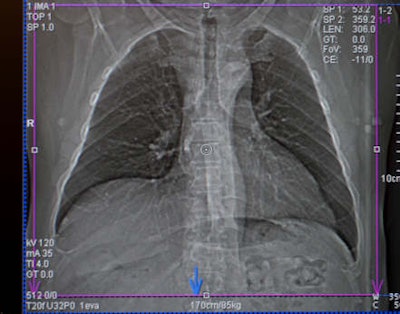

Around 90% of the 49 respondents used automatic dose modulation, a feature of most modern CT scanners that can modulate the dose per section. As a lung scan covers the shoulder bone, for example, more radiation will be applied, while lower down for other organs, radiation dose will be reduced by up to 30%, explained Prosch, who is section chief of thoracic radiology at the Medical University of Vienna. Other possibilities include adjusting the tube potential (kVp) or current to the tube.

"If you don't want to accept the presets provided by the vendor, you can adjust the dose parameters to the patient's age and weight, in addition to using the dose modulation tool," he said. For example, thin patients could be scanned with 100 kVp compared with 120 kVp in 'normal'-sized patients.

"The message we want to send is that state-of-the art CT protocols should include volume datasets with dose modulation switched on and the tube potential adjusted to the age and size of the patient," Prosch added. "While many radiologists use dose modulation tools, not all define the kVp depending on the patient."